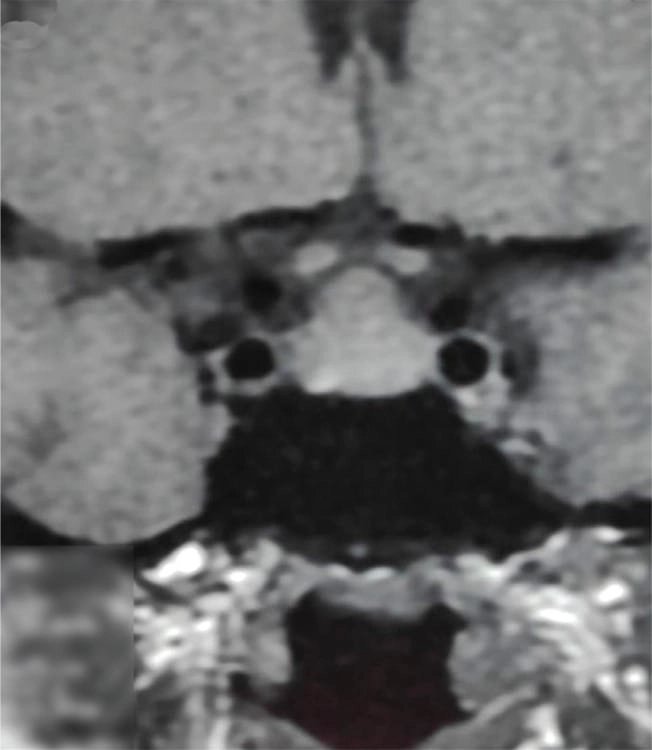

তবে পিটুইটারি হাইপারপ্লাসিয়া দেখা যায় প্রাইমারি গনাডাল, অ্যাডরিনাল বা হাইপোথাইরয়েডিজমের মত এন্ড অর্গান ইনসাফিসিয়েন্সিতে। বিশেষ করে, অব্যবহৃত প্রাইমারি হাইপোথাইরয়েডিজমে পিটুইটারি হাইপারপ্লাসিয়া পূর্বের ধারণার তুলনায় অনেক বেশি দেখা যায়। ২০১৯ সাল পর্যন্ত এরকম ১০৫টি কেস রিপোর্ট করা হয়েছে। এই ধরনের হাইপারপ্লাসিয়া গম্বুজ-আকৃতির (dome-shaped) হয়ে অপটিক কায়াজমাকে চেপে ধরতে পারে, যার ফলে অপারেশনের প্রয়োজন পড়তে পারে—যেমনটা আমাদের তৃতীয় কেসে ঘটেছিল।

MRI-তে এই হাইপারপ্লাসিয়া সাধারণত গম্বুজ-আকৃতির ও সমমিত হয় এবং হোমোজেনাস সিগনাল ইন্টেনসিটি দেখায়, যেখানে সাধারণ নন-ফাংশনাল পিটুইটারি অ্যাডেনোমা নানা আকার ও অসমতা নিয়ে দেখা যায়।